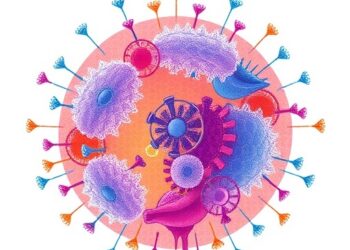

From Immunosuppression to Immune Harmony: Advancing Regulatory T Cell Therapy in Organ Transplantation

Organ transplantation has long been the definitive treatment for patients suffering from end-stage organ failure, yet the journey post-transplant has...